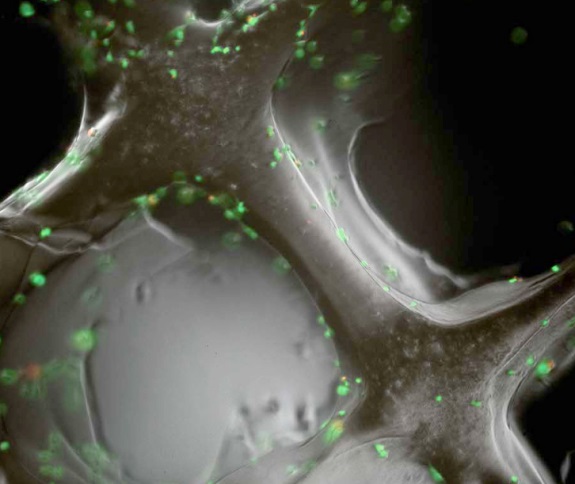

So far, they have tested some bioactive nanoparticles based on calcium on the membrane of a chicken embryo and found that blood vessels formed in it and that the cartilage ossified forming a mature bone. The tests were carried out in mice and the result was also positive. The creators of this innovative product point out that, after three years, the prosthesis would have become a bone of its own. Although it could be applied in any part of the body, it seems that the first objective would be to test it in the maxillo-facial area. Experts estimate that more than a year may pass before human trials are conducted.